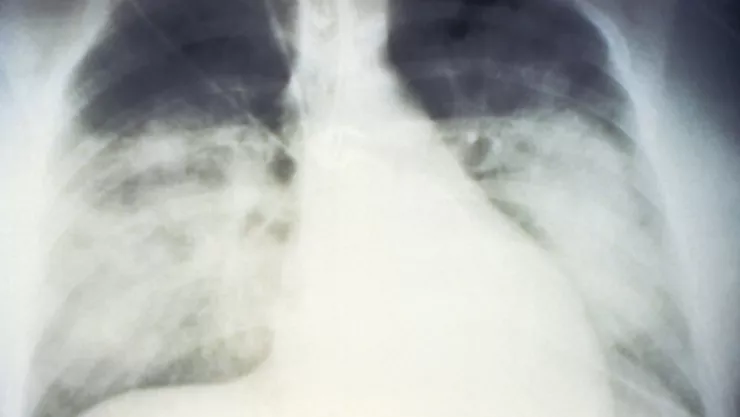

Una mujer de 20 años cuyos pulmones quedaron dañados por la COVID-19 recibió un doble trasplante de ese órgano en Chicago, informaron este jueves autoridades del Hospital Northwestern.

La paciente debió ser intubada con un respirador artificial y conectada a una máquina llamada ECMO (oxigenación por membrana extracorpórea), que reemplaza el corazón y los pulmones para oxigenar y hacer circular la sangre en el cuerpo.